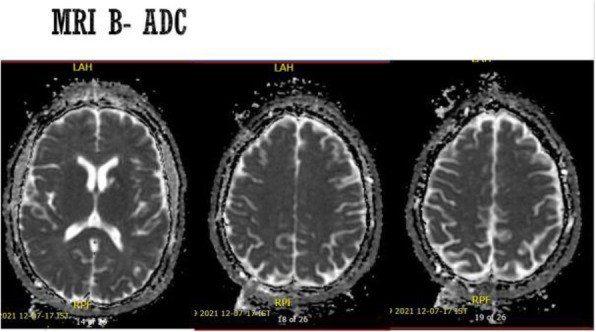

Objective: The mechanisms behind the transformation of episodic migraine to chronic migraine and vice versa have not yet been elucidated. Epigenetic changes are implicated in this process. If treatment results in conversion back to episodic migraine these epigenetic processes might also be reverted. We aimed to identify DNA methylation changes associated with treatment response in chronic migraine patients with medication overuse.

Methods: A longitudinal epigenome-wide association study was performed as part of the Chronification and Reversibility of Migraine (CHARM) study. Blood was taken from chronic migraine patients (n = 98) at baseline and after a 12-week withdrawal period. Treatment responders, patients with ≥ 50% reduction in monthly headache days (MHD), were compared with non-responders to identify methylation changes associated with treatment response. Similarly, ≥ 50% versus < 50% reduction in monthly migraine days (MMD) was compared. Sex-specific analyses were performed. Finally, it was evaluated whether DNA methylation status at baseline was predictive of treatment response after t = 12 weeks.

Results: At the genome-wide level, a change in DNA methylation at one CpG site within an intron of the HDAC4 gene was associated with MHD response (p = 9.42×10–8) (Fig 1A). Sex-specific analyses revealed two CpG sites associated with MHD response, proximal to DLGAP2 for women (p = 1.11x10-7) and STS5/AKIP1 for men (p = 8.67x10-8). Five CpG sites were associated with MMD response in men: ZAN (p = 2.41x10-8), ZNF248 (p = 2.52x10-8), H4C2 (p = 2.87x10-8), between RIT2/SYT4 (p = 4.29x10-8), and between NRXN1/ASB3 (p = 6.44x10-8). Baseline methylation at one CpG within MARK3 was predictive of MMD response at 12 weeks.

Conclusion: Global and sex-specific DNA methylation changes are associated with treatment response in chronic migraine. Moreover, DNA methylation status at baseline might be predictive of treatment response.

Fig. 1 (abstract A21).

Manhattan plots from the epigenome-wide association study. Manhattan plot showing the -log10 p value for each CpG site. The threshold for genome wide significance (p <9.42 x 10-1) is indicated by a continues line. The threshold for suggestive genome wide significance (p < 5 x 10-1) is indicated by a striped line. Changes in DNA methylation in monthly headache days (MHD) responders vs non-responders (A): changes in DNA methylation in monthly migraine days (MMD) responders vs non-responders (B). Predictive value of DNA methylation profiles at baseline of favourable treatment response for MHD (C) and MMD (D)